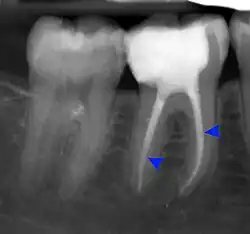

The periodontal ligament becomes inflamed and there may be pain when biting or tapping on the tooth. On an X-ray, bone resorption appears as a radiolucent area around the end of the root, although this does not manifest immediately.[10]: 228 Acute apical periodontitis is characterized by well-localized, spontaneous, persistent, moderate to severe pain.[6]: 125–135 The alveolar process may be tender to palpation over the roots. The tooth may be raised in the socket and feel more prominent than the adjacent teeth.[6]: 125–135

- Radiographs utilized to find dental caries and bone loss laterally or at the apex.